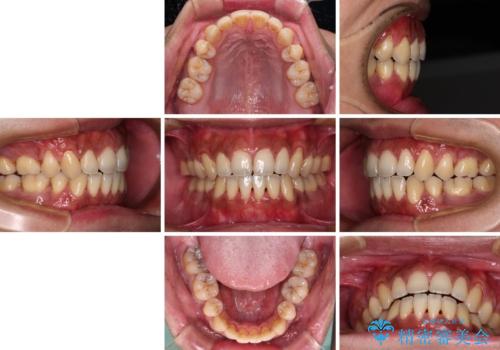

隙間が空いて突出した前歯を治したい ワイヤー装置による抜歯矯正

- 上下前歯の隙間と口元の出っ張った感じを気にして来院された患者様です。

上下の隙間は舌突出癖によるもので、またその癖により前歯が前方に出ている状態でした。

口元の出っ張りを改善するため、上下左右第一小臼歯4本を抜去し、ワイヤー装置にて矯正治療を行うこととしました。

舌の突出癖を改善するためのトレーニングを指導していましたが、なかなか改善することができず、ワイヤー装置を外してからも上下前歯に隙間ができやすい状況でした。